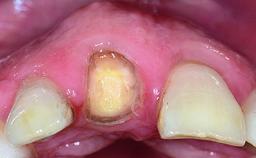

A 30-year-old patient presented at our clinic with a chief complaint of pain in her endodontically treated right maxillary central incisor (tooth 11) with a post-and-core and a fixed single crown. She had a very high lip line, a medium to thin soft-tissue phenotype, and a medium scalloped gingival contour. She also had high esthetic expectations because of her young age and beautiful smile. However, her expectations were realistic and she understood the risks of the treatment. At the initial clinical examination there was a slight mobility of tooth 11; no fistula was observed. The patient also had a single crown on the adjacent tooth 21. Both restorations were old and esthetically deficient. A digital periapical radiograph showed a very small periapical radiolucency, a thick intraradicular post, and no separation between root fragments.

Defining Characteristics One missing tooth to be replaced by an implant-borne prosthesis

Defining Characteristics One missing tooth to be replaced by an implant-borne crown